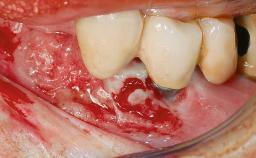

A 27-year-old male was referred to the periodontist for assessment and management of implant site 41. The implant had been placed nine years previously and restored with a screw-retained single crown. The patient was a cigarette smoker in good general health. He reported he had reduced his smoking habit from 25 cigarettes per day to 15 cigarettes per day in the previous six months. On examination, there was calculus and plaque present at the lower anterior teeth and at implant site 41. Localized attachment loss was observed at teeth 32 and 42, with 2–3 mm of gingival recession. At implant site 41, there were 8–9 mm probing depths with suppuration and bleeding on probing.